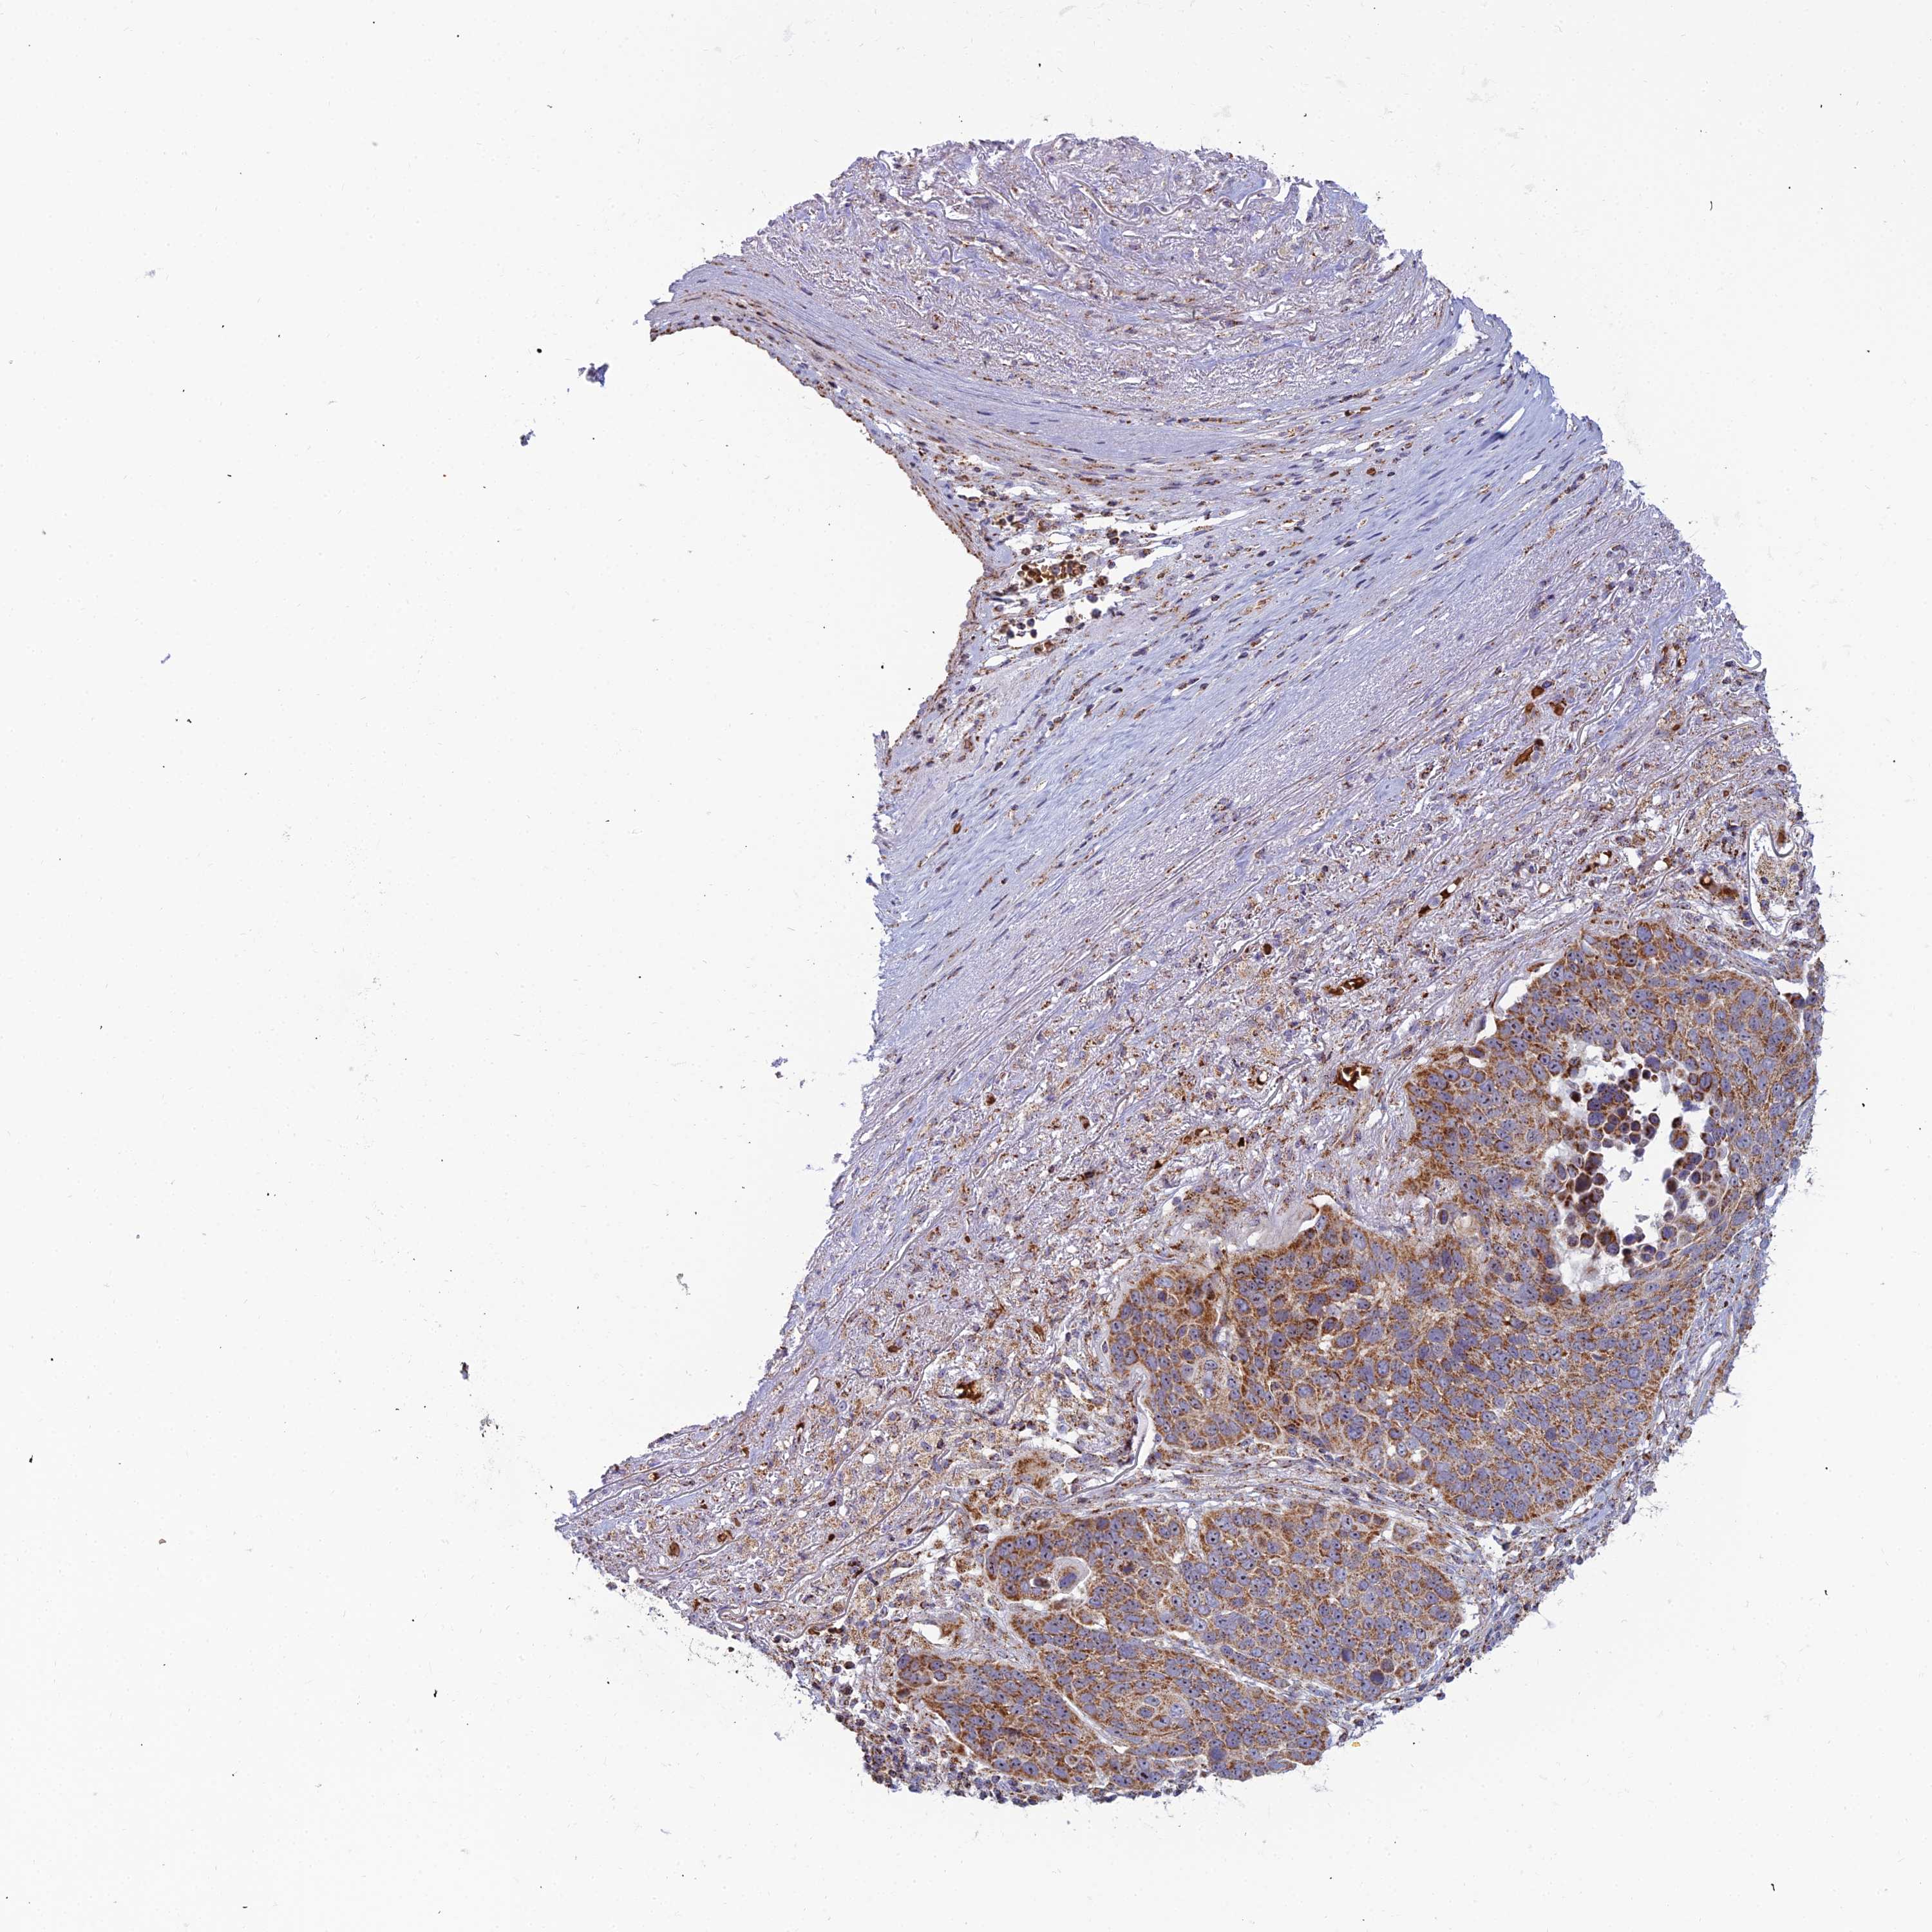

TCGA RNA samplesi

RNA-seq data is reported as average FPKM (number Fragments Per Kilobase of exon per Million reads), generated by the The Cancer Genome Atlas (TCGA) .

Normal distribution across the dataset is visualized with box plots, shown as median and 25th and 75th percentiles. Points are displayed as outliers if they are above or below 1.5 times the interquartile range. FPKM values of the individual samples are presented next to the box plot.

Average pTPM 0.0

Number of samples 497